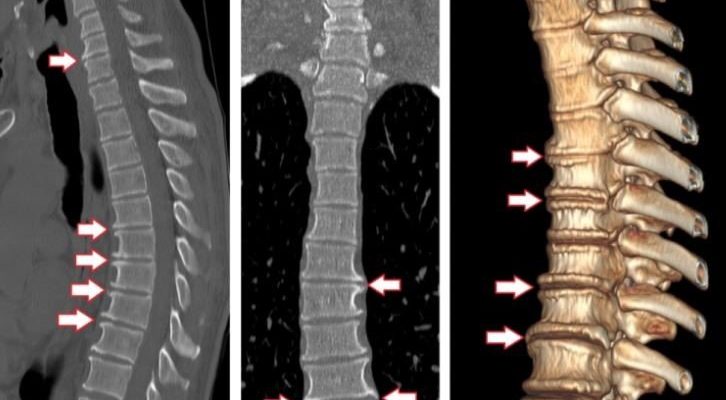

Иногда радиолог должен быстро отреагировать лечащему врачу, например, в случае травмы позвоночника. Компьютерная томография позволяет идентифицировать травму, ее местоположение и диагностировать осложнения, такие как компрессия спинного мозга. Хирург быстро получает необходимую ему информацию перед операцией.

Компьютерная томография намного быстрее (по сравнению с МРТ) и лучше «видит» кости. Это позволяет создавать трехмерные реконструкции для более точной оценки патологии.